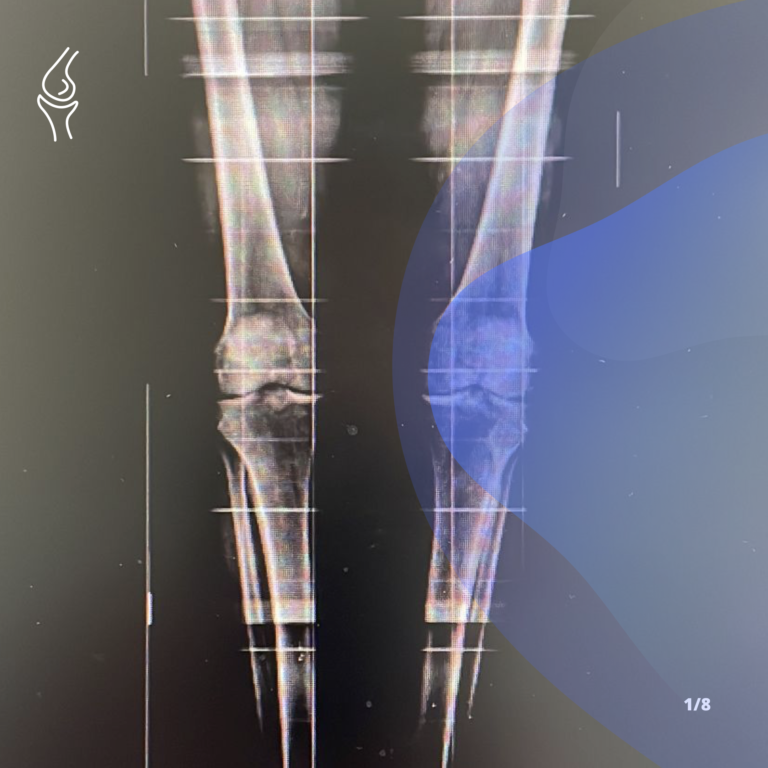

Gonartrosi – Intervento di protesi di ginocchio

Chirurgia robotica nella protesi di ginocchio

Artrosi di ginocchio – Introduzione e sintomatologia